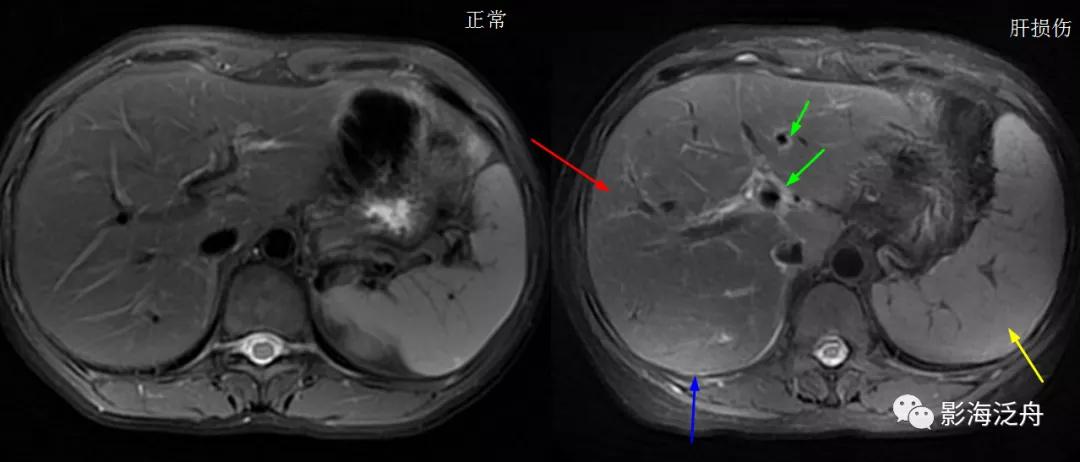

同一患者的T2WI抑脂序列图像,肝实质信号显著减低(红箭),同层面脾实质信号亦明显减低(黄箭),注意椎体及附件的信号也有明显减低(绿箭)。

将该患者与正常人的T2WI抑脂图像放在一起对比观察,用以加深印象。注意观察肝实质、脾实质、椎体及附件的信号变化。

遗传性血色病患者,肝实质(红箭)及椎体(绿箭)信号在T2WI抑脂序列上明显减低,而脾脏信号未明显减低(黄箭)。

注意该患者的肝脏体积略缩小,肝缘欠光整,肝裂增宽,脾大,已经出现比较明显的肝硬化倾向。